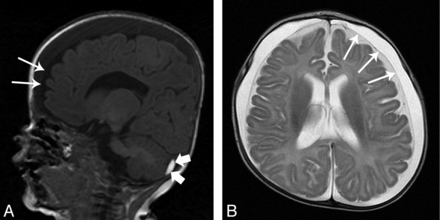

MR imaging scan of a 5-month-old female infant who showed a sudden increase of head circumference (from 50th to 97th percentile within 1 month). Frontoparietal SDHys (maximum width of 11 mm) as well as enlarged subarachnoid spaces (maximum width of 4 mm) were found on both sides (A, sagittal T1-weighted image; B, axial T2-weighted image; thin arrows indicate position of the subarachnoid membrane). In addition, a small subacute SDH was diagnosed in the left posterior cranial fossa beneath the tentorium cerebelli (A, small thick arrows indicate subdural blood). In the preceding months, periodic sonography scans of the head did not ever show any abnormalities with respect to the subdural or subarachnoidal space. Ophthalmologic examination revealed sub- and epiretinal hemorrhages distributed over the whole fundus area of both eyes. These retinal hemorrhages were not present yet in a check-up examination 1 month after birth. As further clinical diagnostics have ruled out coagulopathies, neoplastic diseases, and metabolic disorders, the presence of SDH and retinal hemorrhage prove substantial (sub)acute head trauma and therefore strongly suggest child abuse (AHT). The enlarged subarachnoid spaces, found after the trauma diagnosis, have rather to be regarded as consequence and not as source (see “BESS” section). Hence, the SDHy in this well-documented case can be regarded as a result of acute injury.

Benign enlargement of the subarachnoid space. While in CT (A), BESS could be misdiagnosed as SDHy, MR imaging (B, T1-weighted image; C, T2-weighted image) clearly demonstrates the presence of BESS. Note the vessels (thin arrows) spanning through the subarachnoid space. The small black arrows in B point at the subarachnoid membrane.